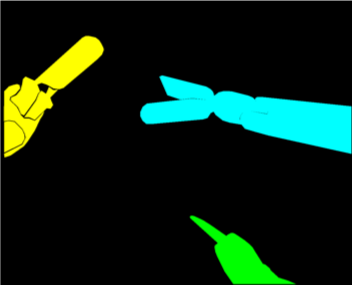

Our challenge was made up of 3 sub-problems. The first was binary instrument segmentation, where each frame was separated into da Vinci Xi instruments and a background class, which contained an ultrasound probe, surgical clips and porcine tissues. The second task was instrument part segmentation, where we scored the participants on whether they could correctly segment each articulating part of the instrument (see Fig. 3). Our final task was to segment and classify the instruments (see Fig. 4).

We provided the first 225 frames of 8 sequences as training data and kept the last 75 frames of those 8 sequences as test data. 2 of the full 300 frame sequences were kept as test sequences. Test labels were kept hidden from the participants. Our datasets contain 7 different robotic surgical instruments. The Large Needle Driver, Prograsp Forceps, Monopolar Curved Scissors, Cadiere Forceps, Bipolar Forceps, Vessel Sealer and additionally a drop-in ultrasound probe, which is typically held in the jaws of the Prograsp Forceps instrument. Samples from the training datasets are depicted in Fig. 2 and examples of the different instrument types are shown in Figure 3 and 4.

IV-D Type Segmentation

The final challenge was to identify each instrument type from the list of Large Needle Driver, Prograsp Forceps, Monopolar Curved Scissors, Vessel Sealer, Fenestrated Bipolar Forceps and Grasping Retractor (see Fig. 4). Only 6 teams participated in this challenge, due particularly to the significant increase in difficulty in recognizing many of the da Vinci instruments from one another.